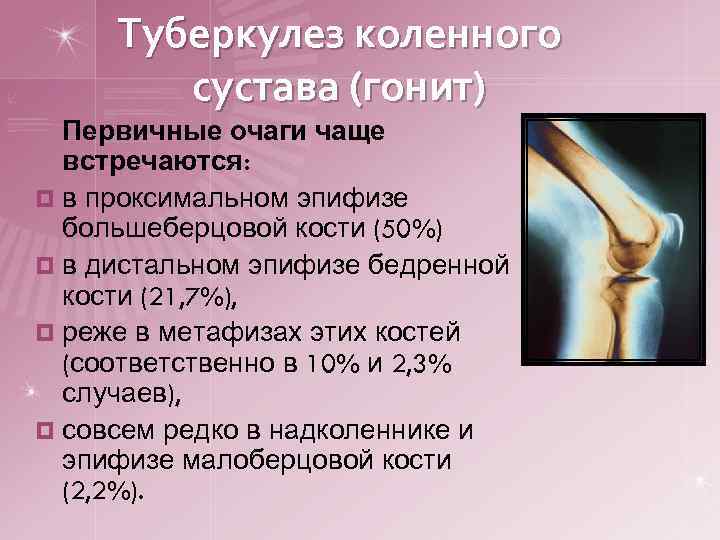

Туберкулез коленного сустава (гонит) Первичные очаги чаще встречаются: ¤ в проксимальном эпифизе большеберцовой кости (50%) ¤ в дистальном эпифизе бедренной кости (21, 7%), ¤ реже в метафизах этих костей (соответственно в 10% и 2, 3% случаев), ¤ совсем редко в надколеннике и эпифизе малоберцовой кости (2, 2%).